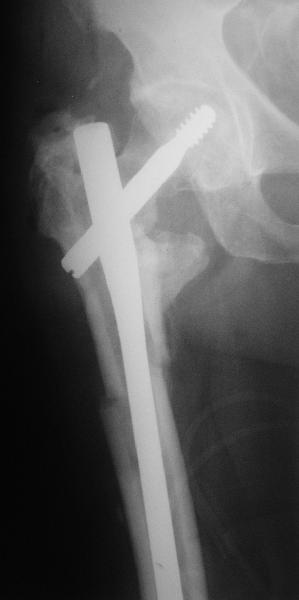

Если есть сильное желание фиксировать все-таки гвоздем, советовал бы ввести мощный "джойстик" параллельно оси шейки бедра близко к ее задней стенке, сделать поперечную межвертельную остеотомию и использовать дистрактор таз-бедро.

Поскольку в нашем случае выявилась подвижность, мы наложили дистрактор таз-бедро на 3 дня, и сделали остеосинтез гаммой без остеотомии. То, что произошла "корригирующая остеоклазия" в подвертельной области, выявили после введения гвоздя. Пациент уже уехал домой, будем наблюдать.